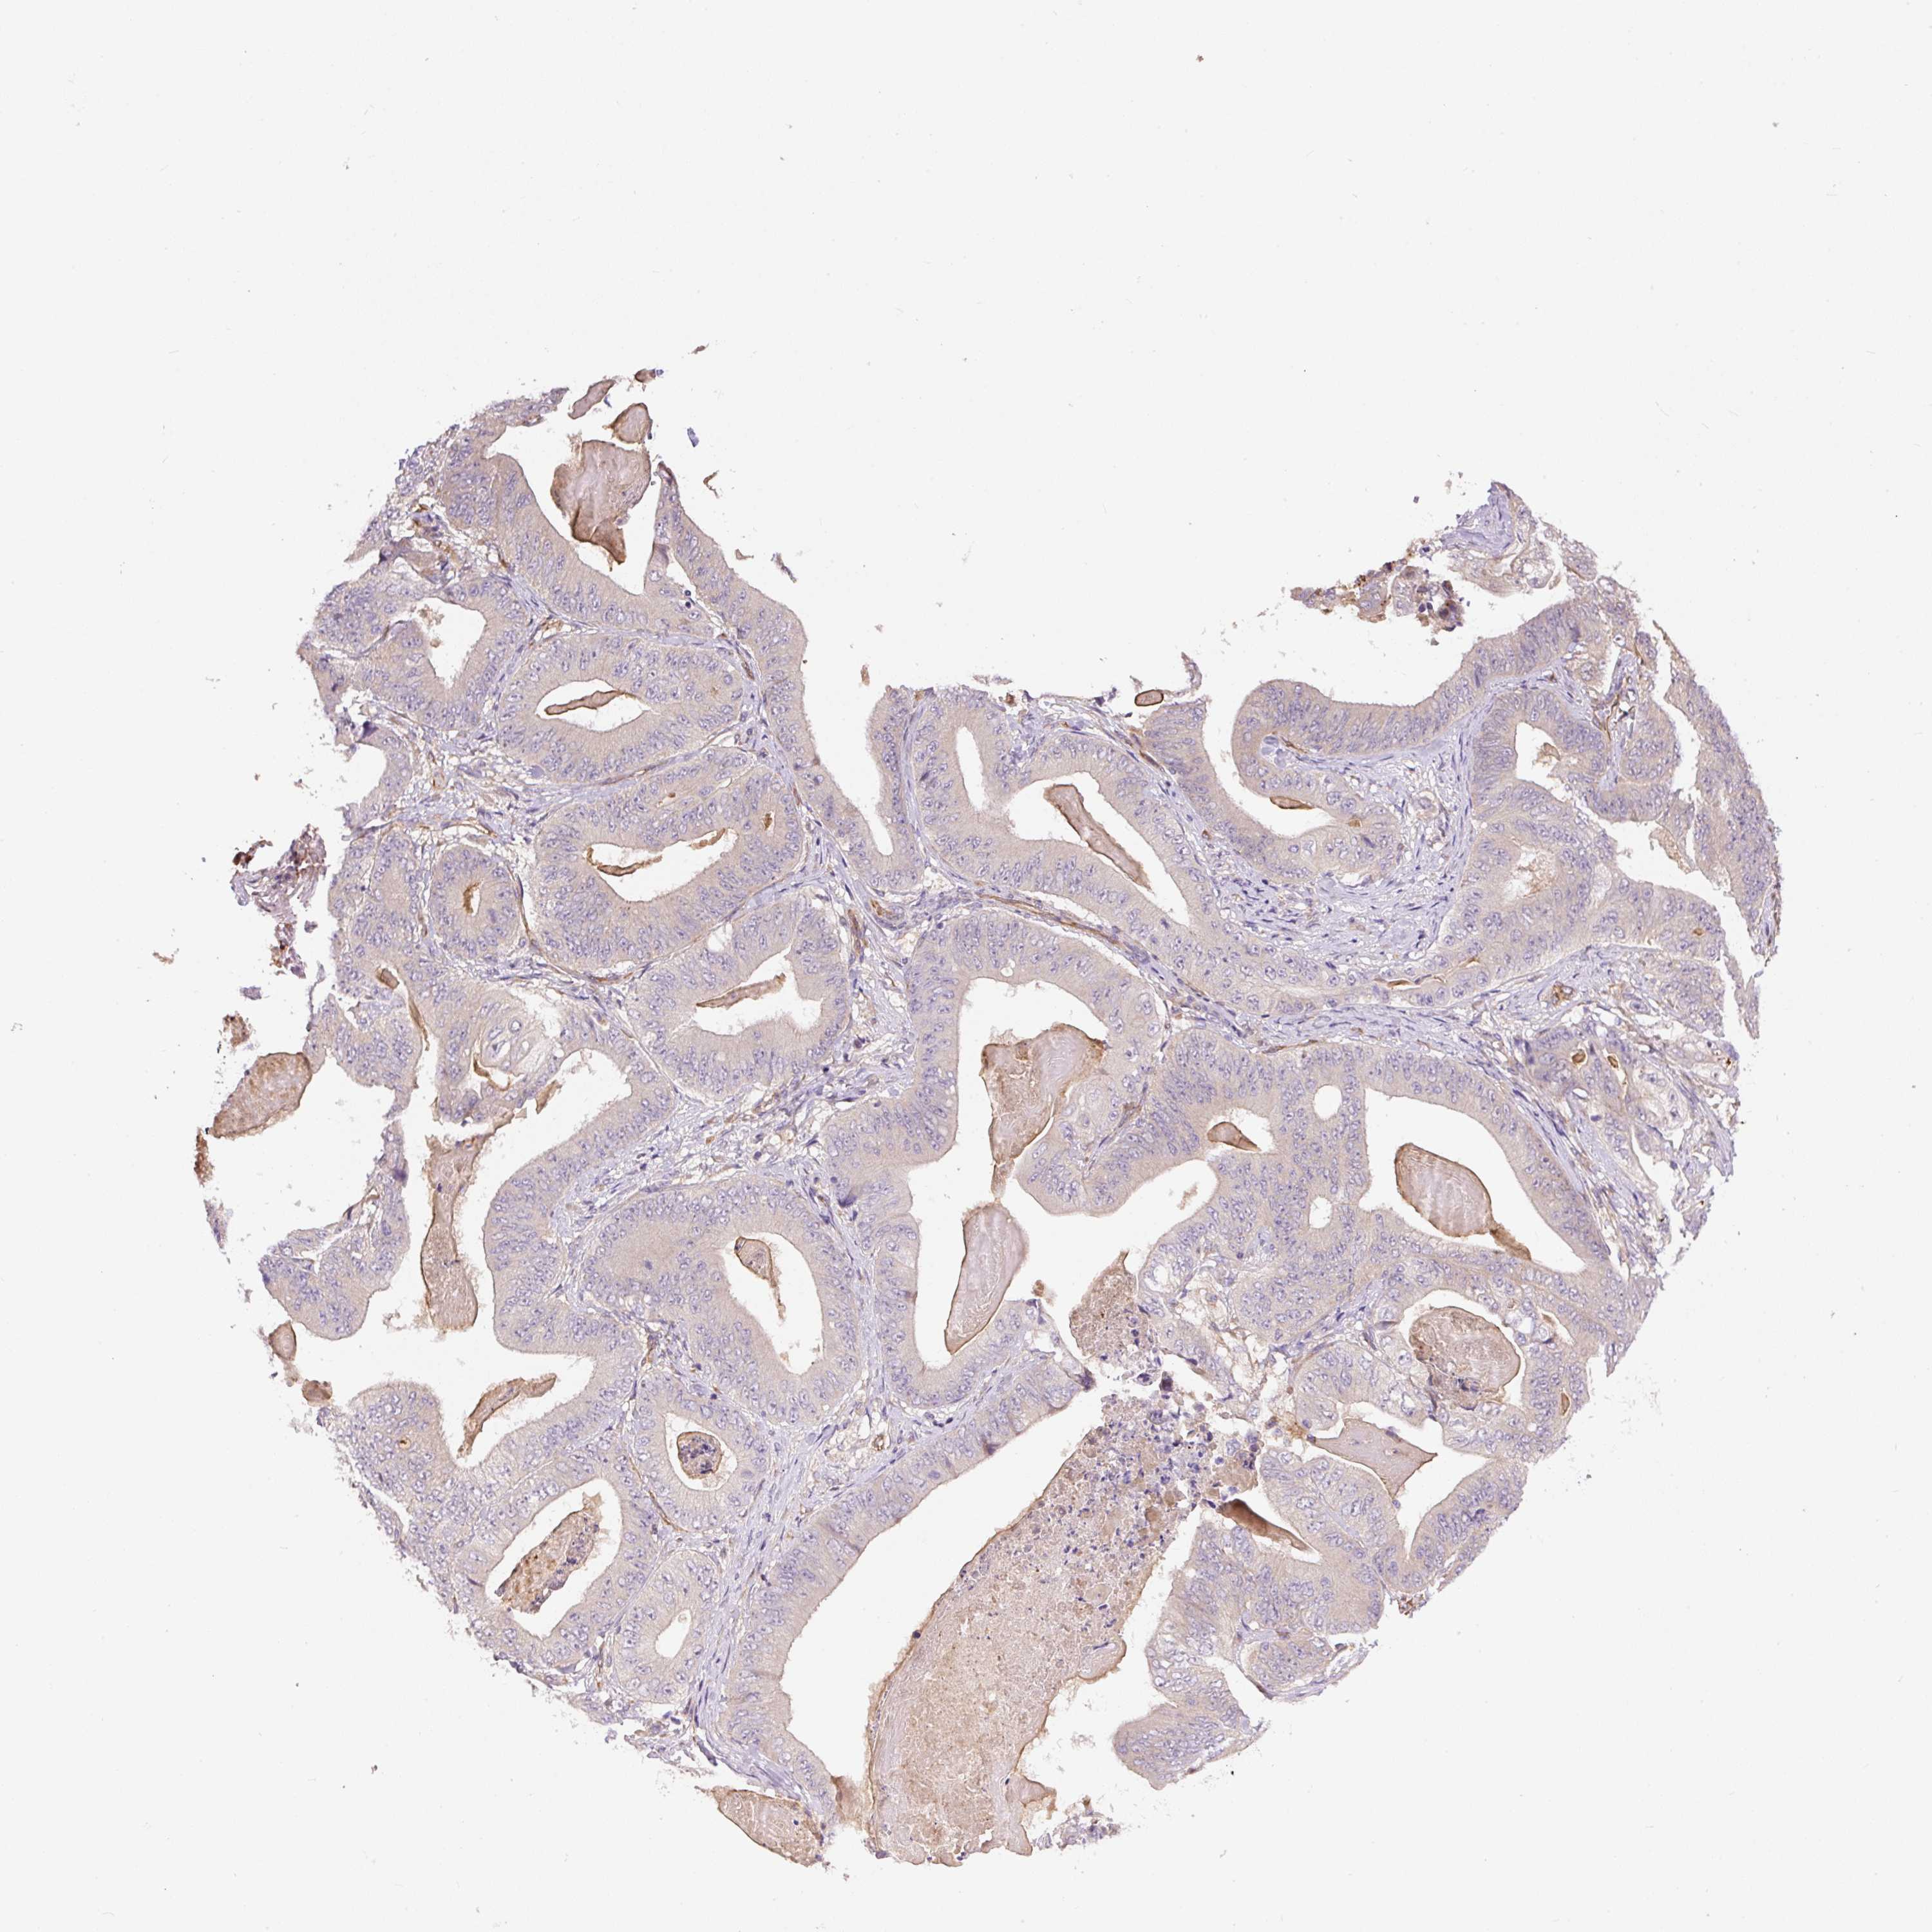

STOMACH CANCER - Protein expressioni

A mouse-over function shows sample information and annotation data. Click on an image to view it in a full screen mode. Samples can be filtered based on level of antibody staining by selecting one or several of the following categories: high, medium, low and not detected. The assay and annotation is described here.

Note that samples used for immunohistochemistry by the Human Protein Atlas do not correspond to samples in the TCGA dataset.

Antibody stainingi

Antibody staining in the annotated cell types in the current human tissue is reported as not detected, low, medium, or high, based on conventional immunohistochemistry profiling in selected tissues. This score is based on the combination of the staining intensity and fraction of stained cells.

Each image is clickable and will lead to virtual microscopy that enables deeper exploration of all samples and also displays staining intensity scores, fraction scores and subcellular localization as well as patient and tissue information for each sample.

Antibody HPA043900

Antibody CAB004541

Staining

High

Medium

Low

Not detected

Intensity

Strong

Moderate

Weak

Negative

Quantity

>75%

75%-25%

<25%

None

Location

Nuclear

Cytoplasmic/membranous

Cytoplasmic/membranous,nuclear

Adenocarcinoma, NOS

Adenocarcinoma, High grade